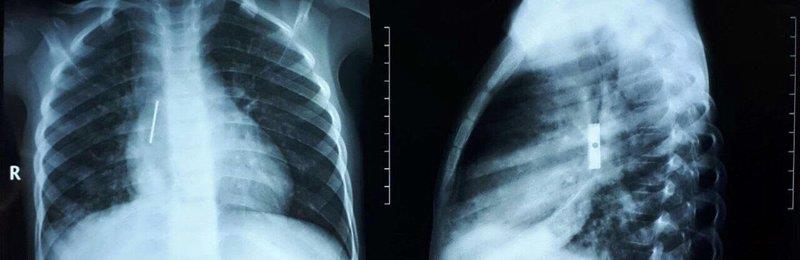

أُجريت عملية جراحية لاستخراج "شفرة مبراة" من القصبة الهوائية لطفل يبلغ من العمر أربع سنوات، في مستشفى الملك عبدالعزيز التخصصي بسكاكا.

وكان الطفل قد وصل إلى مستشفى الأمير متعب بعدما ابتلع جسماً غريباً استقر في القصبة الهوائية.

وبعد إجراء الفحوصات تم اكتشاف وجود "شفرة مبراة" طولها 2 سم، ويُعتقد وجودها على مدى ما بين ثلاثة أسابيع إلى شهر.

وبرغم صعوبة العملية نظراً لحدوث التهابات بسبب طول المدة؛ إلا أن الجراحة تكللت بالنجاح وخرج الطفل في حالة جيدة.